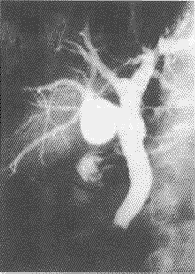

图6 胆总管增粗,下段约5cm范围充盈缺损,残端正不规则改变,可见“双管征”肝总管扭曲、胰管增粗,手术病理证实为胰头癌

102例被检查者,成功93例,失败9例,成功率91.2%,肝内胆管分支显影1~4级78例,1~3级20例,左肝管较右肝管显影长且略粗,胰管显影90例,胆囊不显影27例,显影未见异常6例。87例经手术证实,其中胆囊增生性疾病5例;结石组46例(胆囊结石19例,胆总管结石10例,二者混合型12例,肝内胆管结石5例):肿瘤组19例(其中胰头癌8例,胆总管癌8例,壶腹部癌及肝内胆管癌各1例);炎症组9例(胆管炎7例,胰腺炎2例);胆道手术后狭窄8例。和手术病理对照,ERCP的诊断符合率是93.1%。胆囊增生性疾病5例中3例为胆囊腺肌瘤病,2例为胆囊胆固醇沉着症。这5例因临床表现与慢性胆囊炎相似,初诊为慢性胆囊炎,而ERCP能显示胆囊的形态及其病理改变,手术前得到确诊。可见胆囊底部有一宽基的充盈缺损突入腔内,约1cm×0.5cm边缘不光整有裂隙状透光影,胆囊体周边可见多发的小憩室有造影剂充盈的特征性表现图(图1,见封四)。胆囊胆固醇沉着症2例,可见胆囊较小,边缘不光整,可见均匀剌状突起呈草莓样改变(图2,见封四)。胆系结石46例,其中胆总管内结石10例,胆囊结石19例,同时可见胆囊、胆总管结石12例。肝内胆管结石5例(图3、4,见封四)。行ERCP前,临床初诊为胆系结石40例,结石的部位、大小不明确,另6例结石较大造成胆道梗阻而诊为梗阻性黄疸。行ERCP后结石部位、大小都很明确。胰胆系肿瘤19例。8例胰头癌显示不同范围胆总管下端狭窄和阻塞,呈不规则样改变。“双管征”为胰腺癌的特征,表现主胰管及胆管截然中断,其中有3例表现胆总管狭窄和移位。肝外胆管癌:(1)病变部位可见到边缘不规则或锯齿状的僵硬狭窄,近侧肝管明显扩张:(2)病变部胆管完全闭塞梗阻:(3)病变从胆管的一侧长出形成胆管壁的圆形或不规则充盈缺损(图5、6,见封四)。这一组临床初诊为胰头癌5例,腹壶部肿瘤2例,其余17例诊为梗阻性黄疸。ERCP明确诊断胰头癌8例,肝外胆管癌8例,误诊3例。1例肝内恶性肿瘤表现为肝内胆管压迫移位、狭窄改变,肿瘤致肝内胆管梗阻引起局部扩张。这1例临床初诊为梗阻性黄疸,ERCP误诊为胆管炎。炎症9例,慢性胰腺炎表现为胰管扩张,呈蛇形屈曲,细微分支不规则扩张,胆管炎表现为边缘对称性光整的狭窄,范围2~4cm(图7,见封四)。这一组临床初诊为慢性胰腺炎3例,其余6例诊为梗阻性黄疸。ERCP明确诊断慢性胰腺炎2例,胆管炎5例,误诊为胆管癌2例。胆道手术后8例,这一组临床初诊为胆道术后狭窄,但ERCP可清晰显示胆道手术后狭窄的部位、程度和范围(图8,见封四)。